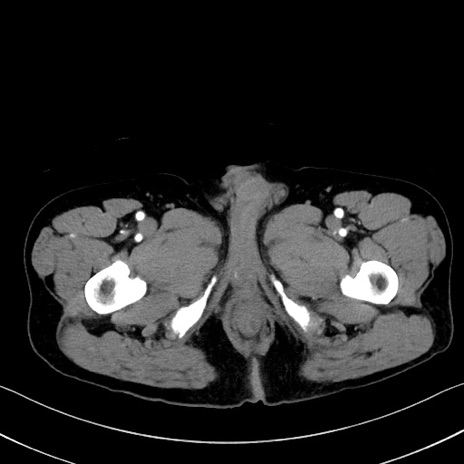

症例35(横断像)

【症例】70歳代 男性

【主訴】腹部膨満、嘔吐

【現病歴】昨日より腹部膨満感出現。本日増悪し、仙痛出現。嘔吐あり、受診。

【既往歴】糖尿病、胆摘後

【身体所見】BP 149/80mmHg、HR 74/min、BT 35.9℃、腹部:膨満、軟、圧痛なし。腸雑音減弱あり。上腹部正中切開瘢痕あり。

【データ】WBC 13500、CRP 1.72